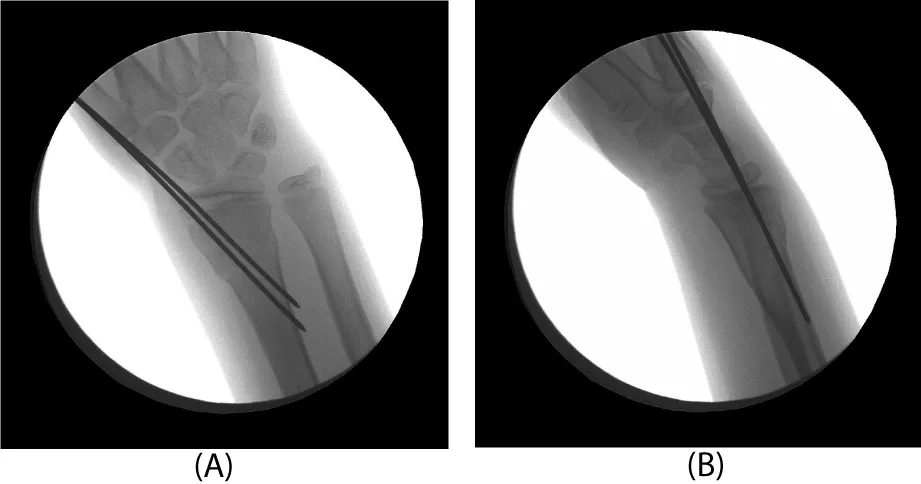

After pre-operative education and informed consent was obtained, the patient was taken back to the operating room for a complex distal radius osteotomy. Care was taken to recover radial length and realign the sigmoid notch of the distal radius relative to the head of the ulna at the distal radioulnar joint per the pre-operative plan and template. In order to recover length, the plate was first applied to the radius and then removed for the osteotomy. It was then reapplied to the distal fragment with locking screws. The plate was then reduced to the radial shaft proximally. Once length was obtained, the radius was secured to the radial shaft with a locking and a non-locking screw (Figure 5). The large trapezoidal metaphyseal defect was then filled with pure cancellous autograft obtained from the ipsilateral iliac crest (Figure 6). A 40mm acetabular reamer was used for this purpose, starting on the outer table and reaming toward, but not violating, the inner table. The remaining radial physis that remained open (ulnarly) was closed with a small burr under image control. The distal ulnar physis was similarly closed through a small ulnar incision to prevent further progression of growth mismatch (Figure 7). At 3 months following the osteotomy, radiographs showed complete healing with incorporation of the bone graft. In addition, the distal ulnar physis had closed. The patient regained full wrist range of motion with 75o extension, 90o flexion, 85o pronation and supination. This was symmetric with his contralateral side. His grip strength was 80 pounds bilaterally. He denied any pain or wrist symptoms and returned to sports and weightlifting. Final follow-up at one year revealed full mobility and symmetrical wrist and forearm motion (no measureable side to side differences). Radiographs showed maturation of the bone graft with remodeling (Figure 8).